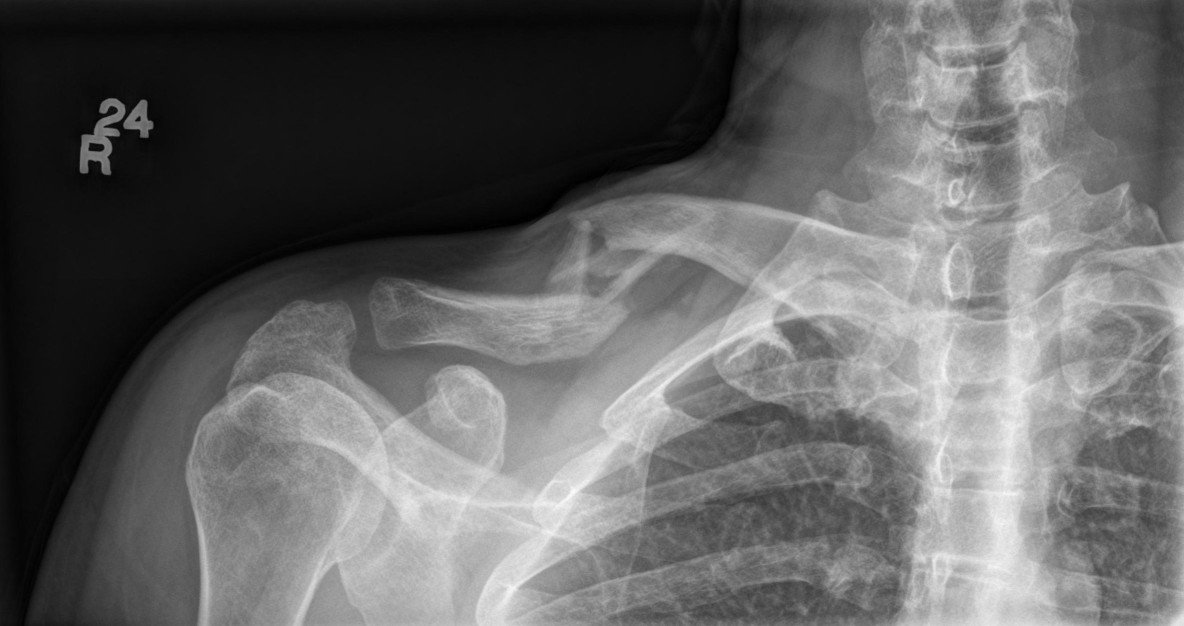

It's been a while since I have been able to update the news section, in 2010 I was diagnosed with a permanent neck injury and in March 2011 I was involved in a motorcycle accident on my way home from holidays, I managed to break my RH clavicle, RH Metacarpal (which was pinned) and LH Thumb, I was off work for 3 months due to my incapacitation and as of October my last x-ray showed that the clavicle was just healing but not healed.

Clavicle%20(1184%20x%20626).jpg